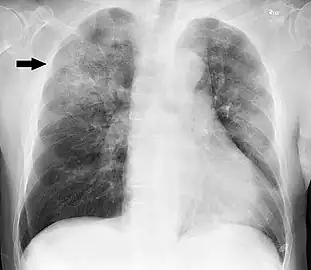

| Chest X-ray of a pneumonia caused by influenza and Haemophilus influenzae, with patchy consolidations, mainly in the right upper lobe (arrow) | |

A chest radiograph is frequently used in diagnosis.[20] In people with mild disease, imaging is needed only in those with potential complications, those not having improved with treatment, or those in which the cause is uncertain.[20][60] If a person is sufficiently sick to require hospitalization, a chest radiograph is recommended.[60] Findings do not always match the severity of disease and do not reliably separate between bacterial infection and viral infection.[20]

X-ray presentations of pneumonia may be classified as lobar pneumonia, bronchopneumonia, lobular pneumonia, and interstitial pneumonia.[66] Bacterial, community-acquired pneumonia classically show lung consolidation of one lung segmental lobe, which is known as lobar pneumonia.[34] However, findings may vary, and other patterns are common in other types of pneumonia.[34] Aspiration pneumonia may present with bilateral opacities primarily in the bases of the lungs and on the right side.[34] Radiographs of viral pneumonia may appear normal, appear hyper-inflated, have bilateral patchy areas, or present similar to bacterial pneumonia with lobar consolidation.[34] Radiologic findings may not be present in the early stages of the disease, especially in the presence of dehydration, or may be difficult to interpret in the obese or those with a history of lung disease.[21] Complications such as pleural effusion may also be found on chest radiographs. Laterolateral chest radiograph can increase the diagnostic accuracy of lung consolidation and pleural effusion.[33]